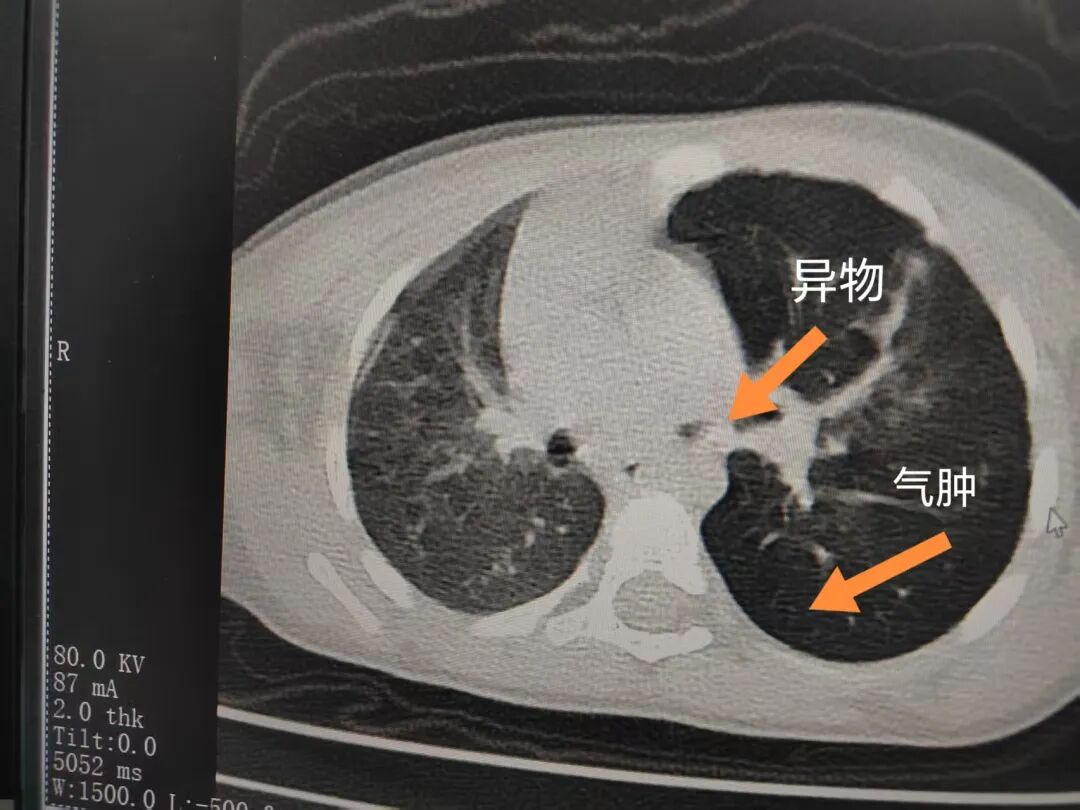

三天后(11月13日),趙寶出現(xiàn)高熱、咳喘加重,家長(zhǎng)著急了,再次帶他來到醫(yī)院。CT檢查顯示左肺過度充氣,左肺上下葉支氣管主干見不規(guī)則高密度影,左肺上葉可見大片狀密度增高影,縱隔窗實(shí)變,提示為“左側(cè)支氣管內(nèi)異物并繼發(fā)性改變,左肺上葉舌段肺膨脹不全”。

市二院小兒呼吸內(nèi)科副主任楊亞娟介紹,異物誤入氣道可能導(dǎo)致氣道阻塞,嚴(yán)重時(shí)可引發(fā)窒息,甚至危及生命。若異物進(jìn)入支氣管,造成不完全堵塞,可引起阻塞性肺氣腫;如完全堵塞支氣管,則可能導(dǎo)致肺組織萎縮,形成肺不張。此外,若異物存留時(shí)間較長(zhǎng),或?yàn)橹参镄援愇?,容易合并?xì)菌感染,產(chǎn)生膿性分泌物,進(jìn)而發(fā)展為肺炎。她強(qiáng)調(diào),盡早診斷并取出異物,是減少并發(fā)癥、降低病死率的關(guān)鍵。